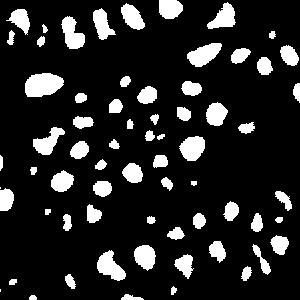

An example is shown in Fig. 2 to illustrate the masks in different rounds of self-training. The foreground nuclei annotation (green pixels) is kept unchanged during the iterations while the background area (pixels in black) grows up gradually. In the third round, the background has high accuracy and the ignored pixels (orange) are almost all nuclei.

(a) image

(b) round 1

(c) round 2

(d) round 3